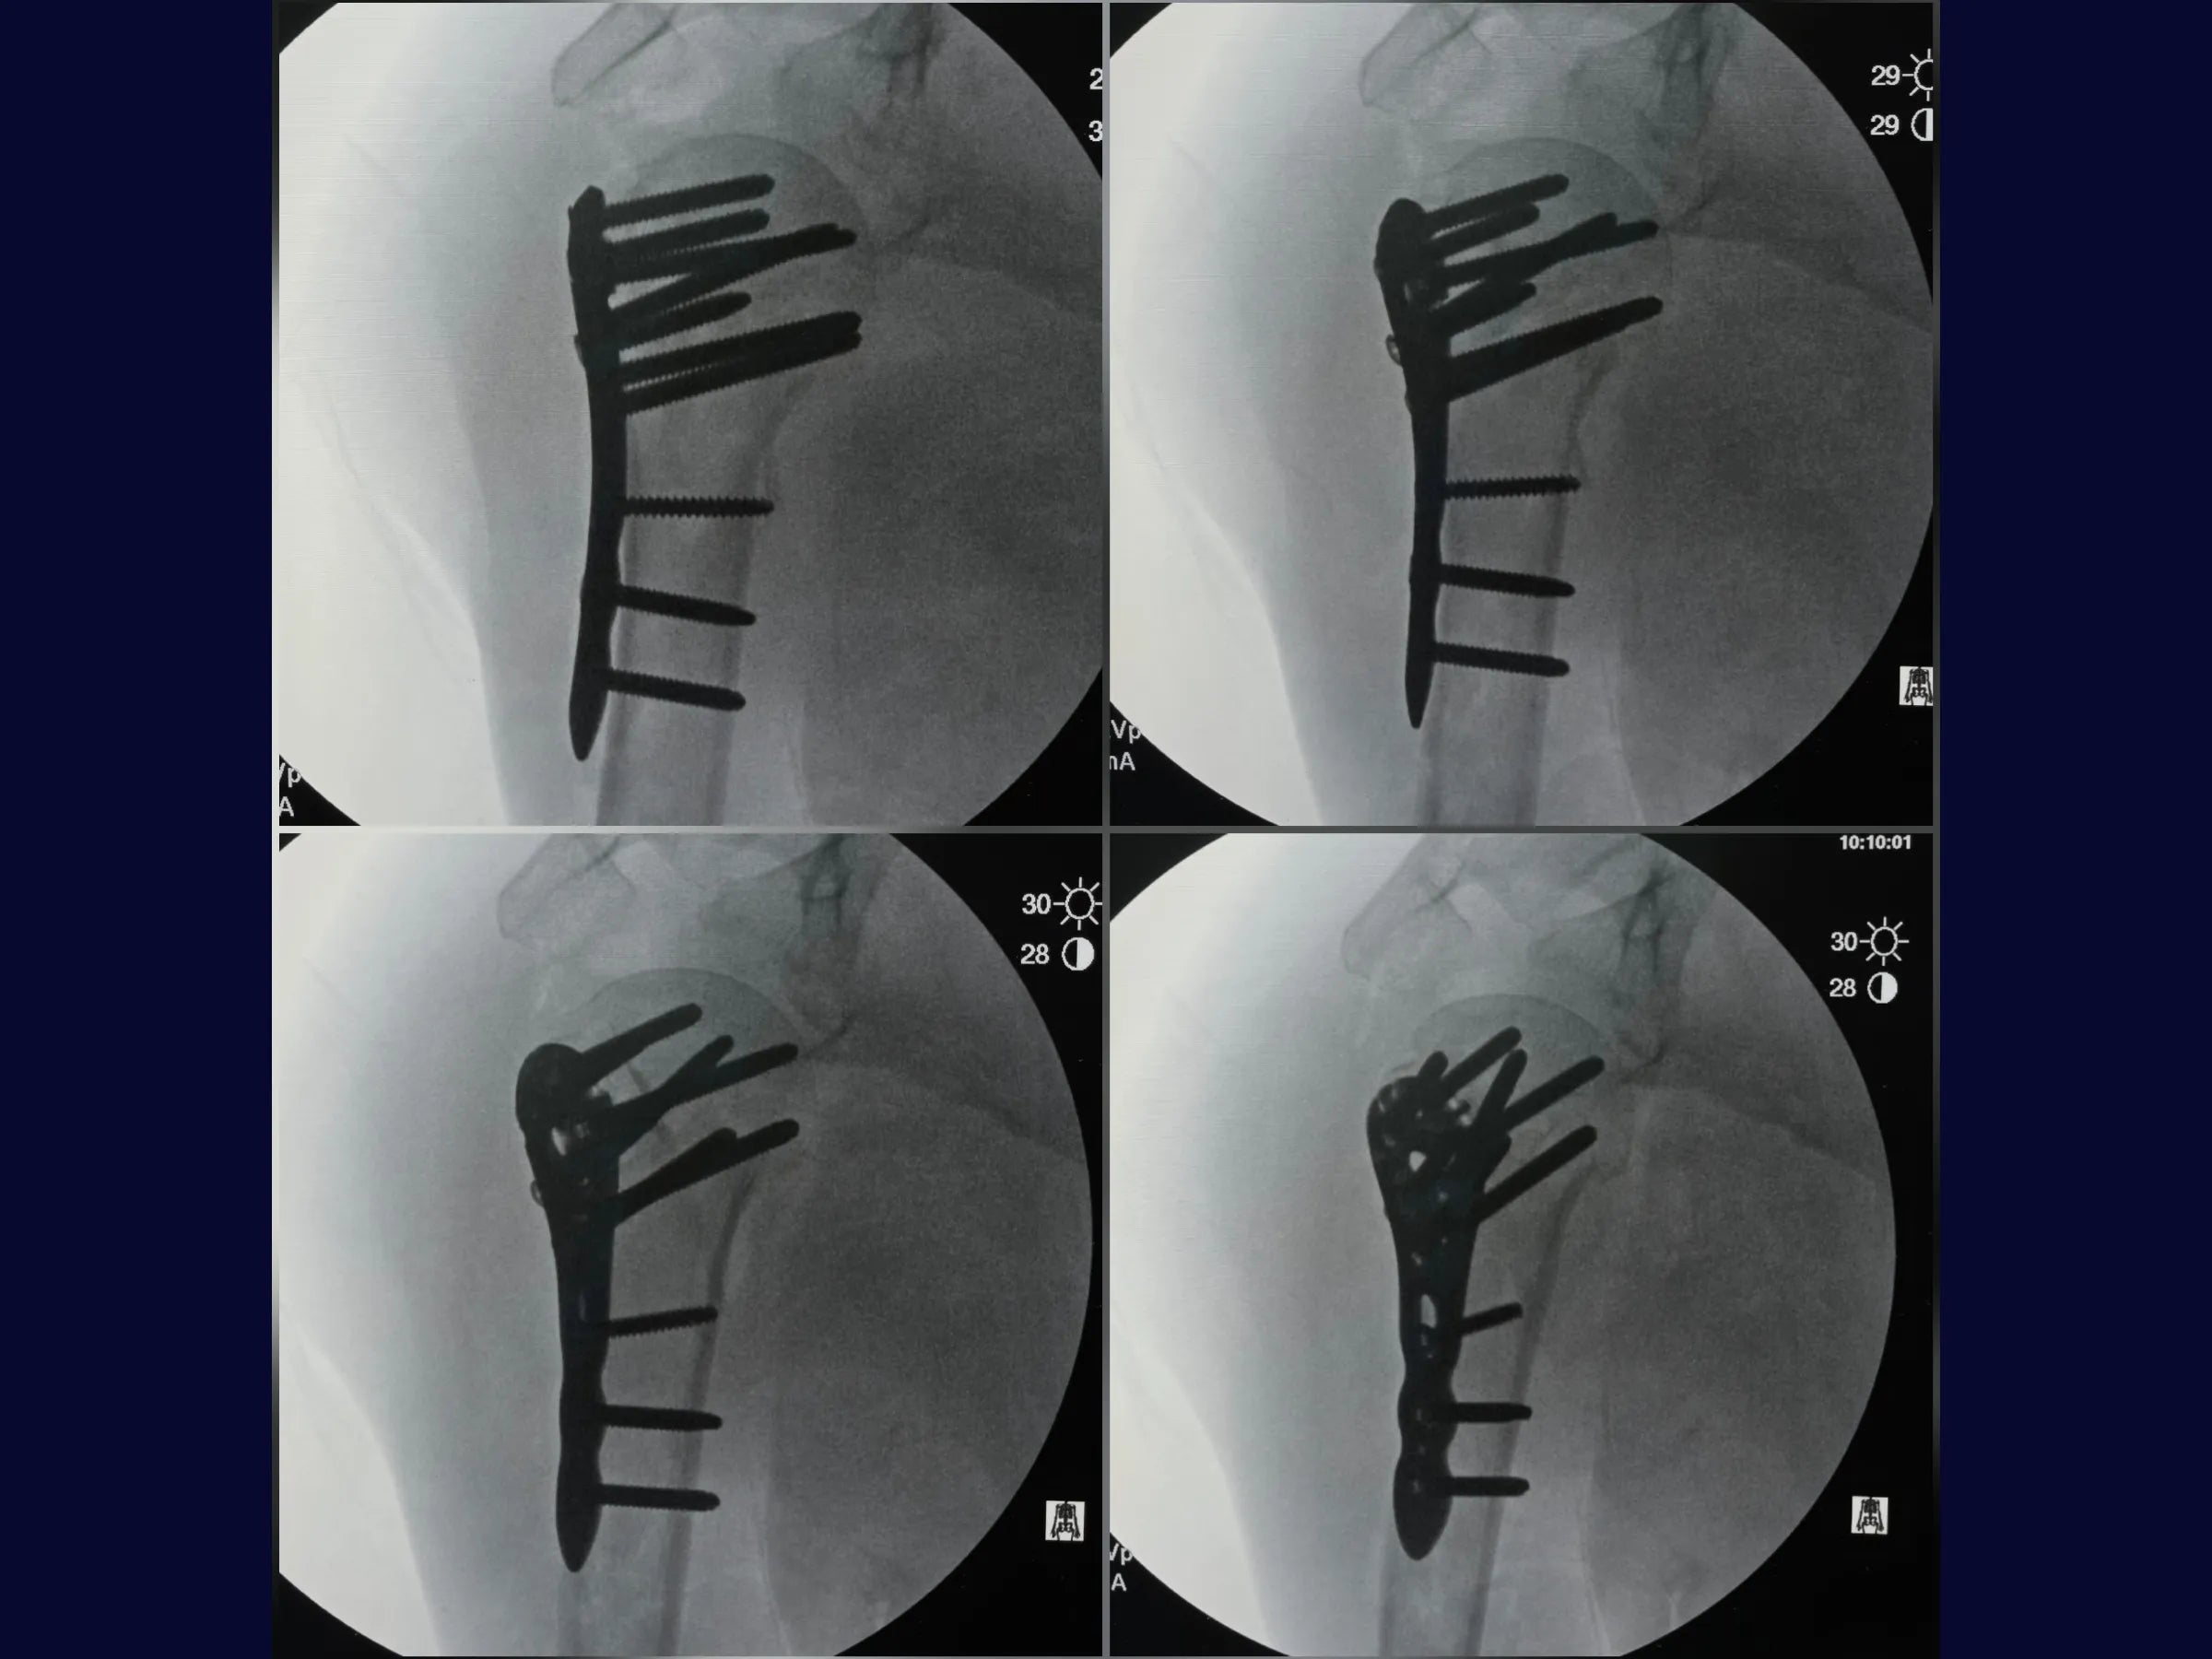

- Fixação com placa bloqueada e parafusos do calcar;

- Estabilidade Biomecânica: Fixação com parafusos do calcar e reforço com suturas de alta resistência.

- Controle Radiográfico e Ajustes Finais: Correção de cisalhamento e simetria com reposicionamento de parafusos.